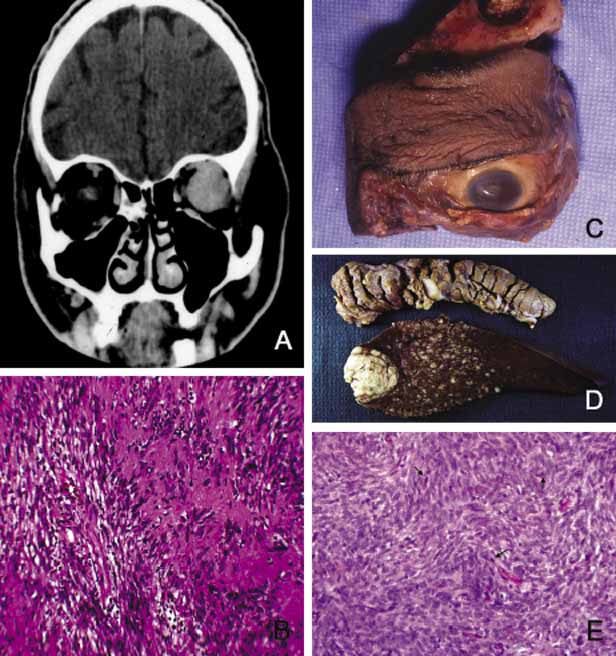

Many metastatic neoplasms originating from other organ systems may find their way to the orbit by hematogenous spread. The most common metastatic malignancies include breast, lung and kidney carcinomas, cutaneous melanoma and rarely sarcomas originating elsewhere in the body.160–162 Tumor-like conditions such as pseudotumors, granulomas, congenital lesions (hamartomas, choriostomas, etc.) that may also invade orbit secondarily are covered elsewhere in this chapter. Both the clinician who evaluates the patient with an orbital space occupying lesion and the pathologist who examines the tissue removed from an orbital mass, must have a working knowledge of the frequency of orbital neoplasms and tumor-like conditions163–166 (Table 4). More commonly encountered acquired orbital neoplasms are detailed. PRIMARY TUMORS Epithelial Neoplasms Primary epithelial neoplasms of the orbit originate from the ductal and acinar epithelium of the lacrimal gland.167,168 The most commonly encountered lacrimal gland tumor is pleomorphic adenoma (benign mixed tumor) (BMT). This neoplasm is known as a “mixed” tumor because it is composed of a mixture of epithelial and stromal elements (Fig. 14). The epithelial elements of the tumor consist of glandular and ductal formations that may develop squamous metaplasia and small keratin filled cysts. The stroma is composed of myxoid tissue that may contain cartilage and bone. In most cases the BMT of the lacrimal gland is multilobulated and surrounded by a fibrous capsule. If additional smaller lobules are present in the vicinity of the main lesion, these satellite nodules are individually encapsulated as well. When malignancy develops within a BMT it is classified according to its predominant histopathologic component as adenocarcinoma within pleomorphic adenoma, adenoid cystic carcinoma, or poorly differentiated carcinoma. Malignant transformation may happen as a rapid growth within an unknown tumor or may take place decades after diagnosis of the BMT.169 Adenoid cystic carcinoma, the most common malignant tumor of the lacrimal gland may also develop de novo. This is a highly malignant neoplasm that can be seen in adolescents and may develop rapid extension into the adjacent structures including the cranium by direct invasion and to the base of the skull by painful perineural invasion.170,171 The histopathologic appearance of adenoid cystic carcinoma may present as several variants including the most common “Swiss cheese” pattern that consists of cribriform clustering of small basophilic tumor cells surounded by thick basement membrane (Fig. 15). Other types including diffuse basaloid, sclerosing, tubular, and comedocarcinoma are known to exist.172 Both benign and malignant tumors of the lacrimal gland present with proptosis and inferior medial displacement of the globe that can readily be demonstrated on CT and MRI studies showing cavitation of the lacrimal fossa in chronic benign lesions and direct invasion of the bony tissues in malignant tumors. Adenocarcinoma developing in BMT (pleomorphic adenocarcinoma, malignant mixed tumor) presents with atypical features within tubular and glandular structures.169 Mucoepidermoid carcinoma of the lacrimal gland consists of diffuse proliferation of atypical squamous cells with abundant vacuolated cytoplasm containing mucin. The clinical course of mucoepidermoid carcinoma is chronic with a relatively favorable prognosis.173,174 Other than true neoplasms, cystic dilatation of the lacrimal gland ductules that is known as dacryops and ectopic lacrimal gland tissue presenting in areas away from the anatomic site of the gland also present as space occupying lesions in the lacrimal fossa.175–177 Mesenchymal Neoplasms The traditional grouping of the primary vascular tumors in the orbit include capillary and cavernous hemangiomas, lymphangioma and arteriovenous malformations. The current thinking is that these lesions represent hamartomas that are made of different tissue components and may be better defined as “vascular hamartomatous lesions.”178 Histopathologic examination of these tumors often reveals mixtures of above listed tissue elements, the symptomatology, clinical course and response to treatment depends on the predominating histopathology. For example, if capillary hemangioma is the dominating element of a vascular tumor it is most often apparent at birth or within the first year, occurs in the anterior orbit and gradually regresses without any treatment. 179 Approximately 70% of capillary hemangiomas regress completely by 7 years of age. Patients with orbital capillary hemangioma may also have similar lesions in other organs. If systemic involvement is extensive, secondary thrombocytopenia known as Kasabach-Merritt syndrome develops. These lesions grossly appear as bright red, strawberry-like masses; histopathologically they are made of sheets of vascular endothelial cells with small lumen formations. Basement membranes surrounding these cells can be clearly identified with a reticulin stain. The predominating cell of the lesion is confirmed to be endothelial cell, by the positive staining for factor VIII, CD31 and CD34. The identification of an intracytoplasmic organelle known as Wiebel-Palade body by transmission electron microscopy also confirms the nature of the tumor cell as vascular endothelium (Fig. 16). For adnexal and orbital capillary hemangioma the treatment options include observation, intralesional and systemic corticosteroids, systemic interferon and in some cases surgical excision and radiation therapy.180–182 Another type of orbital tumor that originates from blood vessels is hemangiopericytoma, which is a pseudoencapsulated spindle cell tumor composed of vascular pericytes183 (Fig. 17). In these tumors the reticulin network surround the individual tumor cells in hemangiopericytoma as opposed to small groups of epithelial cells in capillary hemangioma. In hemangiopericytoma the tumor cells stain positively with factor VIII, CD34, and occasionally vimentin. The histopathologic pattern that may present considerable pleomorphism with increased number of mitotic figures may vary from one zone to the other. The degree of pleomorphism and high number of mitotic figures are not clear cut indications of malignancy; as a matter of fact, the biological behavior of this tumor cannot be determined based on its histopathologic appearance. Metastatases after many years have been described.184 The best treatment for hemangiopericytoma is surgical excision. Cavernous hemangioma is another benign vascular tumor that occurs in adults, usually as a solitary, unilateral lesion, but multiple tumors have been described.185,186 Unlike capillary hemangioma it is not associated with other lesions elsewhere in the body. It is usually located within the muscle cone but may also be seen in extraconal locations and presents with slowly progressive proptosis without too much extraocular motility disturbance (Fig. 18). Gross appearance of cavernous hemangioma is a well encapsulated reddish purple lesion with a sponge-like consistency on its cut surface. Histopathologically, it consists of dilated vascular channels lined by endothelium and smooth muscle and intervening fibrous stroma. The endothelial cells are held together by tight junctions and display basement membrane reduction. Clinical differential diagnosis of cavernous hemangioma on imaging include fibrous histiocytoma, hemangiopericytoma, schwannoma and metastatic tumors.187 Surgical removal of the tumor is the treatment of choice. Another lesion of this category that presents with large cavern formations surrounded by different amounts of fibrous tissue is lymphangioma.188–190 Unlike cavernous hemangioma, however, the space formations in this lesion are not lined by endothelial cells and do not contain vascular smooth muscle; the spaces are lined by flat mesothelial-like cells (Fig. 19). Spontaneous bleeding may take place within these cystic spaces resulting in “chocolate” cysts. In one-third of the cases, lymphoid follicles with germinal centers may be present in the intervening fibrous stroma and some tumors with abundant lymphoid tissue may respond to systemic steroid treatment. Because of the infiltrating nature of this tumor, surgery is not an early option of management; these lesions should be managed conservatively.190 Orbital varix is another orbital vascular lesion that develops as a distention of a venous channel leading to stagnant blood flow resulting in thrombus formation.191 Orbital varices are divided into primary lesions, confined to the orbit and secondary lesions associated with intraorbital and intracranial arteriovenous malformations.54 Vascular hamartomatous lesions may contain arteriovenous malformations with or without abnormal communication between arterial and venous vasculature. These lesions should not be confused with carotid cavernous and dural cavernous fistulas, which affect the orbit secondarily.192 If one clinically suspects an A-V malformation component in an orbital vascular lesion, CT angiogram and arterial and venous angiograms should be used to rule out the connection of the lesion to systemic circulation.193 Color Doppler flow imaging has also been used to examine these tumors. In addition to the above detailed vascular tumors, angiosarcoma, Kaposi sarcoma, intravascular papillary endothelial hyperplasia (IPEH), vascular leiomyoma and angiolymphoid hyperplasia with eosinophilia (Kimura disease), can rarely be encountered in the orbit.194–198 In this chapter, neural neoplasms are covered under two major groups: tumors originating from central nervous system (CNS) tissues, and tumors originating from peripheral nerves. The two most commonly encountered tumors of the optic nerve that involve the orbit are optic nerve glioma and optic nerve meningioma.200 Optic nerve glioma (ONG) is primarily a tumor of childhood.201,202 When it presents in adults a more malignant glioma should be suspected.203 ONG is associated with neurofibromatosis type I (NF-I) with one or both optic nerves involved in approximately 25% of the cases.204 Some authors suggest that patients with NF-I may have a favorable prognosis. In general, the more anterior the glioma, the more favorable the prognosis.205 These tumors produce painless progressive visual loss and proptosis and ophthalmoplegia.206 Optic disc swelling and atrophy is generally present and rarely optociliary shunt vessels may develop.207 Neurofibromatosis (NF) is subdivided into types I and II. It is an autosomal dominant multisystem disease characterized by multiple tumors and developmental abnormalities.208,209 Neurofibromatosis type I presents with numerous ocular adnexal and orbital manifestations including optic nerve and chiasm gliomas and optic nerve sheath meningioma (Fig. 20). Histopathologically ONG is a low-grade pilocytic astrocytoma.210,211 The tumor is composed of proliferating fibrillary astrocytes that may show different degrees of pleomorphism and vascular proliferation (Fig. 21). The axonal component of the nerve is not involved with the neoplastic process during the early stages of the disease. Mitotic figures and necrosis are associated with malignant transformation into higher grades. These tumors show pleomorphic cellular changes, with increased mitotic rate and necrosis. Long standing ONG (”ancient” glioma) may develop degenerative changes including dilated processes of glial cells (Rosenthal fibers) and hyalinization.200 The diagnosis of these tumors has significantly improved with the advances of neural imaging, particularly with MRI and the role of biopsy in the management ONG has become more or less obsolete.212 In unusual cases in which there is rapid tumor enlargement accompanied by visual loss, biopsy may reveal useful information to differentiate between ONG and meningioma and may help in documenting the presence of a malignant glioma. Interpretation of the biopsy sample may be difficult because of the infiltration of the subarachnoid space with pilocytic astrocytes that are similar in appearance to meningeal fibroblasts.213 Another pitfall that should be remembered is that the arachnoidal hyperplasia secondary to ONG may be misinterpreted as a primary meningioma.214 The treatment of ONG includes surgical excision if the extension into the cranium is imminent. Radiation and chemotherapy are generally reserved for patients older than age 5 years with worsening of signs and symptoms.215 Meningioma is a slow-growing tumor originating from the meningoendothelial cells of the arachnoidal layer of the optic nerve or the cranial meninges. These tumors may occur primarily in the optic nerve sheath or extend into the orbit secondarily from the cranial cavity.200 The symptoms of optic nerve meningioma (ONM), which typically affects white, middle-aged females, include slowly progressive, painless loss of vision and proptosis. As the disease progresses, there may be disc edema, orbital ciliary shunts, and optic atrophy.216 Histopathologically meningioma shows varying patterns of meningoendothelial proliferation including sheets of polygonal cells, mixed proliferation of elongated meningoendothelial cells with fibroblasts, and the psammomatous type in which the meningoendothelial cells form eddies to surround calcified psammoma bodies (Fig. 22). Immunohistochemically, they are positive for EMA and vimentin (Fig. 22). Two other types of more aggressive histopathologic patterns are known: the angioblastic and sarcomatous. These lesions have a tendency to recur and extend into adjacent bone and occasionally metastasize. Although a malignant behavior is not predictable in all cases, high mitotic rate implies worse prognosis; cell cycle markers such as MIB-1 may be useful in evaluation of borderline aggressive cases. There is an increased incidence of bilateral and multiple meningiomas in neurofibromatosis I and II.217 ONM is usually diagnosed with ultrasonography, CT and MRI.218 Therefore, biopsy is only needed in atypical cases. Surgical treatment of ONM leads to total loss of vision; therefore, it is saved as a last resort for eyes without vision or for unusually large lesions with potential extension into the cranium. Currently radiation therapy is the treatment of choice from the standpoint of long-term preservation of the vision.219,220 Peripheral nerve tumors of the orbit originate from the ciliary ganglion and from cranial nerves III, IV, V, and VI, which are ensheathed by Schwann cells. Schwannoma (neurolemoma) is a benign tumor that originates from the Schwann cell.221 This adulthood tumor accounts for approximately 1% of all orbital tumors 222 Most cases are solitary and unilateral and have a predilection to the superior orbit originating from the branches of supraorbital or supratrochlear nerves.221–223 Approximately 25% of schwannomas demonstrate enlargement of the superior orbital fissure and invasion of the cavernous sinus on CT and/or MRI.224 Schwannoma generally occurs as an isolated tumor; however, in approximately 10% of cases it is associated with neurofibromatosis.225 Histopathologically this encapsulated tumor is composed of proliferation of Schwann cells that in areas reproduce the pattern of the nerve sheath. The cells that have indistinct cellular borders and oval nuclei form either solid structures (Antoni A pattern) or a loose arrangment in a background of finely granular eosinophilic material (Antoni B pattern) (Fig. 23). Isolated clusters of tumor cells (Verocay bodies) are diagnostic.221,226 Older tumors show degenerative changes with increased areas of myxoid differentiation, collagenation and necrosis. These changes are seen in long-standing tumors that are known as “ancient” schwannomas and on MRI present with a cavitary appearance that can be confused with a cystic orbital tumor.227 Very rarely the schwannoma demonstrates increased cellularity of spindle-shaped cells with pleomorphic nuclei and hyperchromatism.228 The malignant tumor usually presents with a plexiform pattern of irregularly swollen nerve bundles containing spindle-shaped cells. Malignant transformation of schwannoma is very rare but once this occurs the prognosis of “malignant schwannoma” (malignant peripheral nerve sheath tumor) is very poor because of rapid intracranial extension or distant metastasis. Tumor cells of schwannoma stain positive for S-100 protein but the positive immunoreactivity is not specific to this tumor; neurofibroma also demonstrates positive but weaker staining with S-100. On occasion, it may be difficult to distinguish a malignant peripheral nerve sheath tumor from other poorly differentiated sarcomas; in these situations, S-100 and GFAP positivity supports the diagnosis of peripheral nerve sheath origin. Neurofibroma accounts for approximately 2% of all orbital tumors.222 This tumor, which is composed of neoplastic proliferation of Schwann cells, axons, and endoneural fibroblasts, may present as an isolated, diffuse or plexiform lesion. All cases of plexiform tumors and some of the diffuse ones are associated with neurofibromatosis and their other characteristics are also similar.229 The localized type is very rarely associated with neurofibromatosis. The plexiform neurofibroma usually presents at a young age as an eyelid lesion, which has been described with a consistency of “bag of worms.” Histopathologically plexiform neurofibromas consist of intertwined bundles of hypertrophic axons, endoneural fibroblasts, and Schwann cells that are compacted into well-demarcated cylindrical cores (Fig. 20). Diffuse neurofibroma is similar to its plexiform counterpart but the distinct bundle formation is absent. The solitary neurofibroma is also composed of groups of axons, Schwann cells and fibroblasts but it is well circumscribed. All three types stain positive with S-100 protein; however, the reactivity is less intense than schwannoma.230 In patients with neurofibromatosis malignant transformation of neurofibroma into neurofibrosarcoma develops in approximately 20% of cases.231 Choice of treatment for neurofibroma is surgical excision that is easily performed in circumscribed, solitary neurofibromas. This often proves to be very difficult for diffuse and plexiform lesions. Large lesions eventually are treated with exenteration. Other types of peripheral nerve tumors including granular cell tumor, alveolar soft part sarcoma, paraganglioma, melanotic neuroectodermal tumor of infancy, primary neuroblastoma and carcinoid have also been reported to originate in the orbit.232–234 Rhabdomyosarcoma (RMS), which constitutes approximately 1% of all orbital tumors, originates from the primitive mesenchymal cells of the orbital soft tissues, which have the capacity to differentiate toward skeletal muscle.235,236 This sarcoma develops more often in males at approximately the age of 7.237 Based on the predominating histopathological pattern, these tumors are classified into four types: embryonal, alveolar, pleomorphic, and botryoid.238 Pleomorphic and botryoid types are rarely seen in the orbit. Embryonal type is predominantly composed of elongated pleomorphic tumor cells with a centrally located hyperchromatic nucleus surrounded by a considerable amount of eosinophilic cytoplasm (Fig. 24). In embryonal RMS, the tumor cells differentiate along rhabdomyoblastic lines with formation of elongated, spindle cell types (“strap cells”), in which longitudinal and cross striations are sometimes discernible, particularly with phosphotungstic acid-hematoxylin (PTAH) stain. The striations represent the presence of actin and myosin filaments, forming bundles within the cytoplasm of the tumor cell. The banding pattern may be accentuated with the use of immunohistochemical markers (actin, desmin) or with electronmicroscopy.239 Alveolar RMS, however, presents with small nodular tumor masses with a variety of histopathologic patterns; in the prevailing pattern, alveolar tumor cells are loosely adherent to a network of thin interstitial fibrovascular septa; the tumor cells are loosely attached to the connective tissue, and in many areas become freely floating in the alveolar spaces (Fig. 24). Although the prognosis for life in all types of RMS has improved dramatically in recent years because of the multidisciplinary treatment approach, it is still true that embryonal type tumors have a better prognosis than alveolar RMS.240,241 Typical clinical features include the sudden appearance and rapid evolution of unilateral proptosis, associated with early extraocular motility disturbance and extensive eyelid and conjunctival edema. In children who present with this clinical picture, the suspicion of RMS should be high and a biopsy should be performed as quickly as possible. Excisional biopsy is preferred over FNAB, which may lead to erroneous diagnosis because it offers a limited amount of tissue.242 Although chemotherapy and radiation therapy play a significant role in management of these tumors, it is still true that the bulk of the tumor should be removed surgically as much as possible, particularly in anteriorly located lesions.243 Because of different patterns of histopathology several round and spindle cell metastatic and primary neoplasms and pseudosarcomatous lesions including leiomyosarcoma, lymphangioma, malignant peripheral nerve tumors, fibrous histiocytoma, Ewing sarcoma, and metastatic neuroblastoma should be considered in the histopathologic differential diagnosis of RMS.237,244 Immunohistochemical studies (Table 3) and electromicroscopy may be of help in diagnosis of poorly differentiated cases. Because of the morphological overlaps, it is important to wait for the results of permanent histopathologic sections before a management plan is initiated, because benign and inflammatory conditions and pseudotumors may simulate RMS, particularly on frozen-section examination.245,246 Other myogenic tumors of the orbit include smooth muscle tumors, leiomyoma and leiomyosarcoma, which occur very rarely.247–249 Fibrohistiocytic Lesions Some of the spindle cell tumors and tumor-like lesions of the orbit originate from fibroblasts and histiocytic cells. These include fibroma, fibromatosis, fibrosarcoma, and fibrous histiocytoma (FH).250,251 Fibrous histicytoma is the most commonly occurring orbital lesion of this group and according to some it is the most common mesenchymal tumor developing in the adult orbit.252 FH is usually a well-circumscribed lesion, which presents a firm, solid yellowish grey appearance on its cut surface. Histopathologically, it is composed of two primary elements: spindle-shaped fibroblasts and rounded histiocytic cells, which are arranged in an interwoven pattern or in a storiform pattern, radiating from central focal points of condensed collagen (Fig. 25). These tumors can sometimes be confused with hemangioperiocytoma,183,253 as well as other spindle-cell tumors, including solitary fibrous tumor, schwannoma, neurofibroma, meningioma and in cases occurring in children, embryonal rhabdomyosarcoma.254 Although most of these tumors are benign, locally aggressive and malignant lesions are described.255,256 The treatment of FH is surgical excision. Fibrohistiocytic tumors and tumor-like conditions include reactive lesions and neoplasms250,257 (Table 6). Reactive lesions are known as fibromatosis; desmoid and juvenile fibromatosis and nodular faciitis.258,259 Although these lesions are histopathologically benign, they are often locally aggressive and have a high rate of reccurrence, particularly in a restricted anatomic site, such as the orbit. The neoplastic fibrohistiocyic lesions can be broadly categorized into two categories as fibroblastic and fibrohistiocytic tumors. The neoplasms originating exclusively from fibroblasts, namely fibroma and fibrosarcoma, are primarily encountered as a second malignant neoplasm in hereditary retinoblastoma survivors and after radiation treatment.260,261

TABLE 6. Fibrohistiocytic Lesions Originating From Primitive Mesenchymal Cell Lines